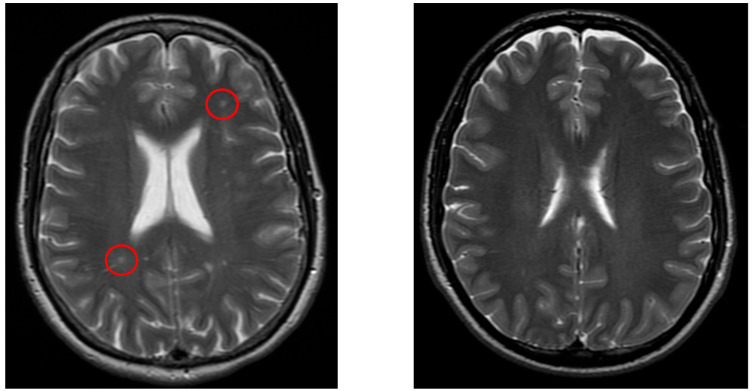

Background/Objectives: Dizziness is a frequent medical complaint with neurological, otolaryngological, and psychological origins. Imaging studies such as CT (Computer Tomography), cervical X-rays, and ultrasound aid diagnosis, while MRI (Magnetic Resonance Imaging) is crucial for detecting brain abnormalities. Our purpose is to identify structural brain changes associated with vertigo, assess pre-MRI diagnostic approaches, and evaluate treatment strategies. Methods: A case-control study of 232 vertigo patients and 232 controls analyzed MRI findings, pre-MRI examinations, symptoms, and treatments. Statistical comparisons were performed using chi-square and t-tests (p < 0.05). Results: White matter lesions, lacunar infarcts, Circle of Willis variations, and sinusitis were significantly more frequent in vertigo patients (p < 0.05). Pre-MRI diagnostics frequently identified atherosclerosis (ultrasound) and spondylosis (X-ray). Common symptoms included headache, imbalance, and visual disturbances. The most frequent post-MRI diagnosis was Benign Paroxysmal Positional Vertigo (BPPV). Treatments included lifestyle modifications, physical therapy (e.g., Epley maneuver), and pharmacological therapies such as betahistine. Conclusions: MRI revealed structural brain changes linked to vertigo. Pre-MRI assessments are essential for ruling out vascular and musculoskeletal causes. A multidisciplinary treatment approach is recommended. Trial Registration: This study was registered in ClinicalTrials.gov with the trial registration number NCT06848712 on 22 February 2025.

Abstract Image